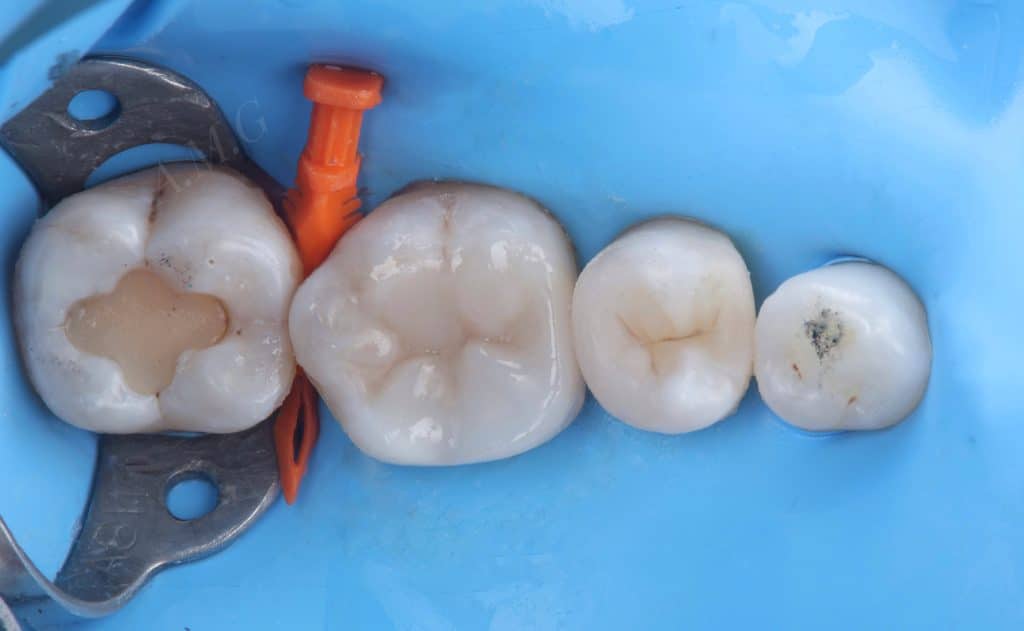

rubber dam isolation and start old restoration &caries removal

caire detector dye applied , peripheral seal zone obtained and then adhesive system applied .

matrix system applied used Garrison green ring after missed wall build up first .